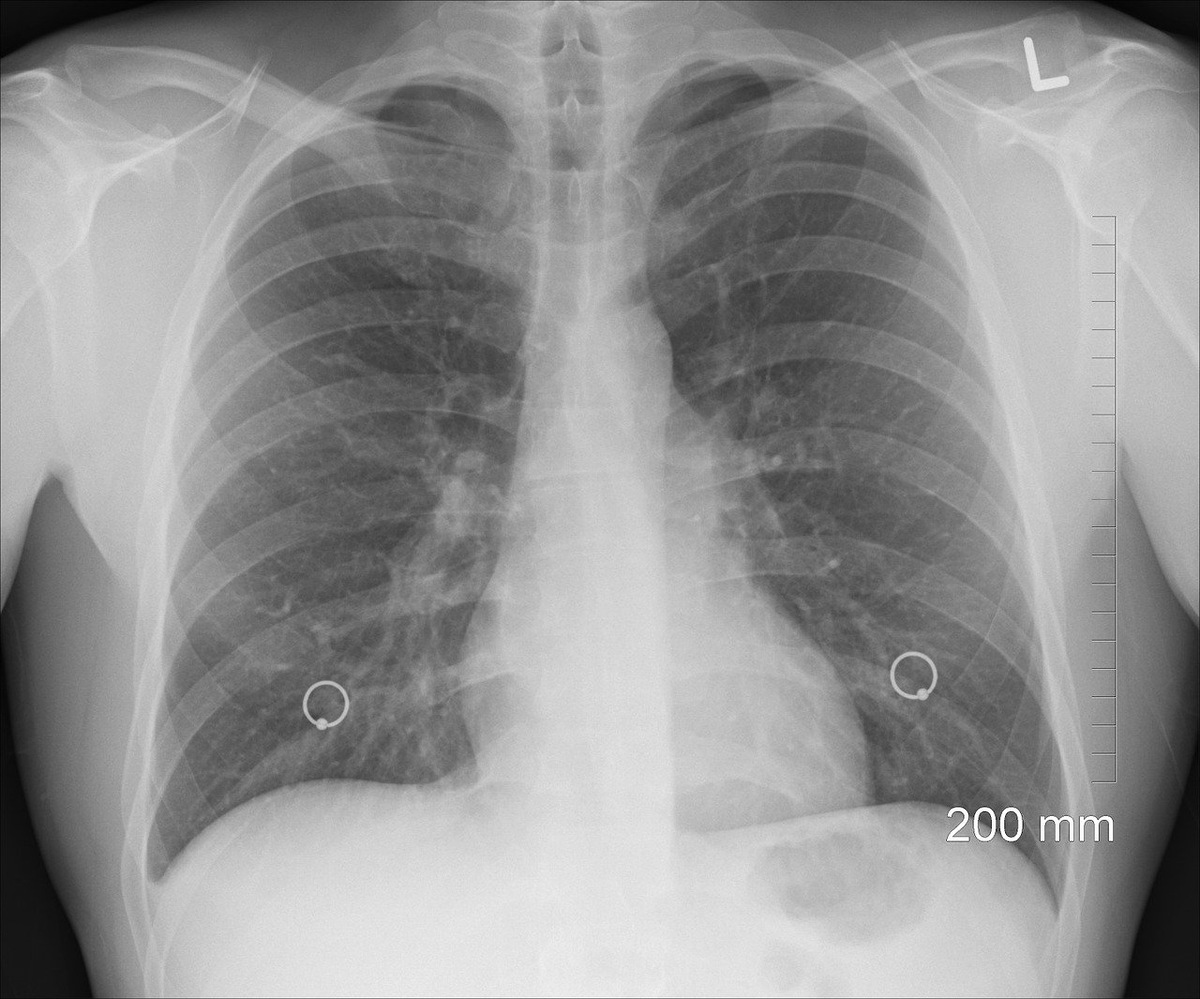

Ради снимка легких вообще приходится ехать за 200 км

Ранее местные врачи оказались в центре скандала из-за того, что отказались госпитализировать пациентку, у которой было поражено больше половины объема легких. В итоге место в госпитале ей нашли, но для этого пациентку пришлось отправлять за пределы Хабаровска.

Позже в подобную ситуацию попала гостья из Петербурга. Она гостила в СовГавани и обратилась в "скорую" с симптомами ОРВИ и повышенным давлением, врачи приехали спустя полсуток и ничего опасного в ее состоянии не нашли, госпитализировать ее не стали, а при повторном вызове из-за резкого ухудшения самочувствия ей посоветовали обратиться в поликлинику по месту жительства и не досаждать медикам неотложки со всякой ерундой. Хабаровчане отмечают, что так сейчас врачи реагируют на многих своих пациентов. При этом пройти обследование. которое может показать состояние легких, могут далеко не все жители региона. Так, например, бикинцам приходится ездить на компьютерную диагностику за 200 км, а результатов ковидных тестов порой ждать по две недели.